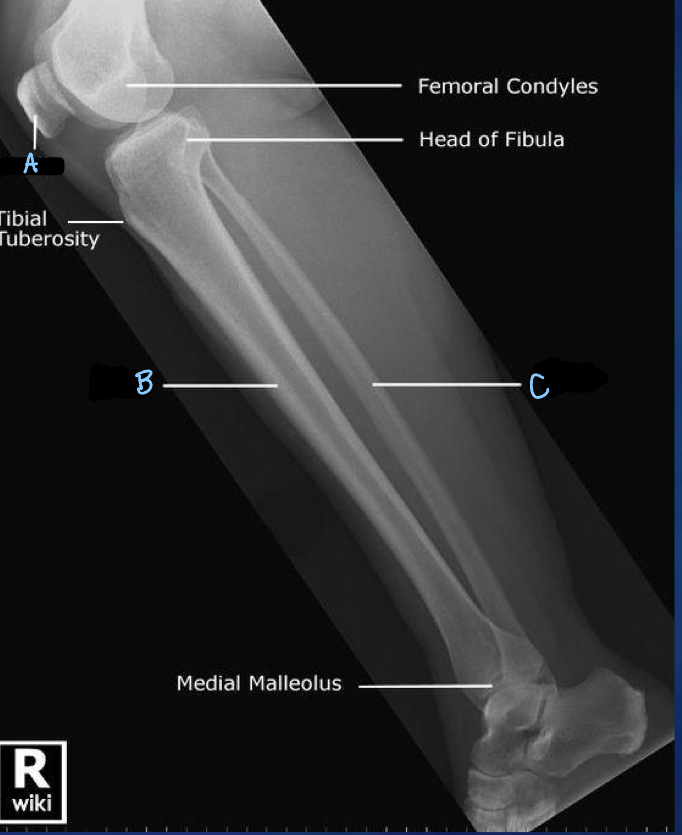

1

Q

What is A?

A

lateral tibial condyle

2

What is B?

fibula

3

What is C?